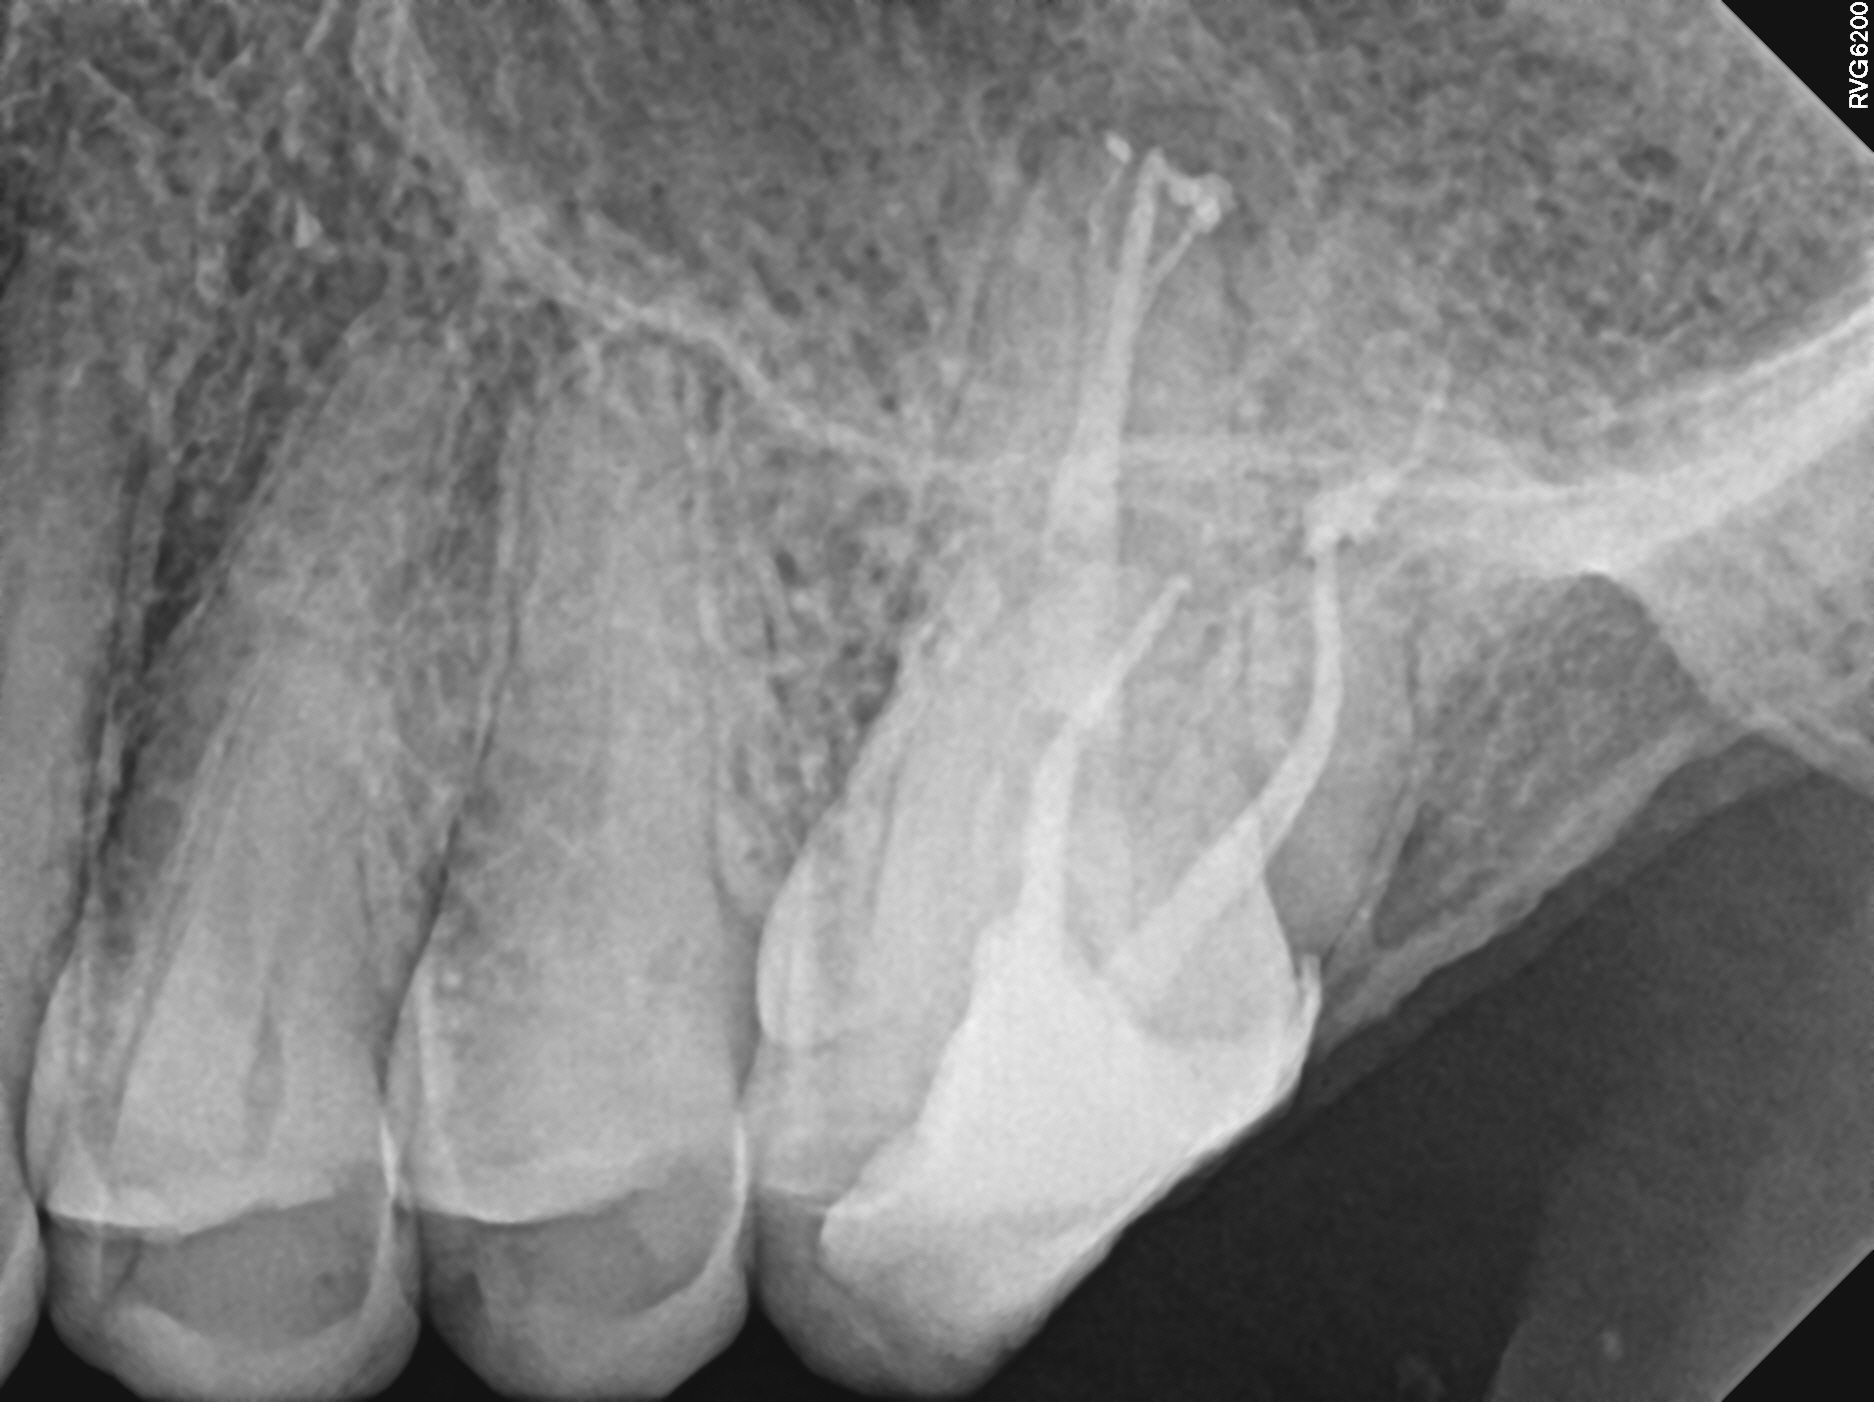

Case 14

An example of a root end surgery (apicoectomy). The tooth had a prior root canal treatment and an instrument broke inside the root. There was also resorption (dissolving) of the root tip by the infection. The broken file blocks treatment in the canal space, so I surgically removed the portions of the root with the instrument and also the portion of the other root with the resorption. The ends of the roots were cleaned and filled. The final X-ray, taken two years later, shows perfect healing.